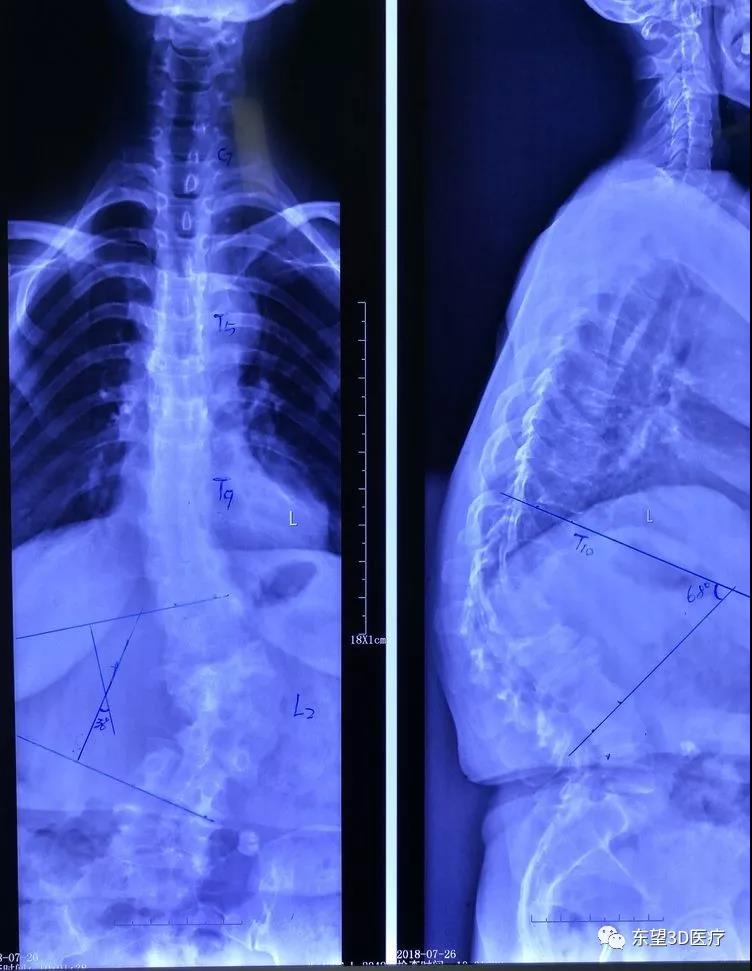

術前全脊柱正側位X片,見腰椎側凸后凸旋轉畸形(女,47歲,跛行腰疼下肢疼痛麻木26年,近年加重,行走約200米就需休息)

\

術前腰椎過屈過伸位及左右bending像,腰椎不穩